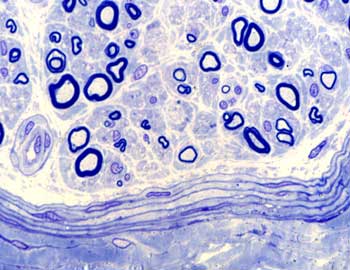

Visión general: una sección de la pared del intestino delgado ha sido seleccionada para mostrar diferentes formas de presentarse las células musculares lisas. A pocos aumentos nos permite observar las vellosidades intestinales como evaginaciones de la mucosa revestidas por un epitelio en el que destacan las células absortivas, y entre ellas las glándulas tubulares rectas que se introducen en profundidad y que ya estudiabamos en la practica de epitelios glandulares. Por debajo de esta capa mucosa, aparece la submucosa y por fuera una capa muscular bien desarrollada responsable del peristaltismo intestinal.

Visión específica: cuando a mayores aumentos pasamos a buscar células musculares lisas hemos de detenernos en tres zonas diferentes. Primero en la propia vellosidad intestinal en cuyo eje conjuntivo aparecen junto con el quilífero central algunas células de esta naturaleza que constituyen el músculo de Brüke, las observamos preferentemente cortadas en sentido longitudinal y aparecen como elementos alongados de núcleo único y central. Posteriormente y tras repasar la ya conocida arquitectura de las glándulas llegamos a su limite inferior en donde una fina capa muscular lisa marca el paso a la submucosa. Se conoce como capa muscular de la mucosa. Tras pasar por esta capa conjuntiva submucosa llegamos a una doble capa de células musculares, las vemos cortadas tanto en sentido longitudinal como transversal constituyendo gruesas túnicas.